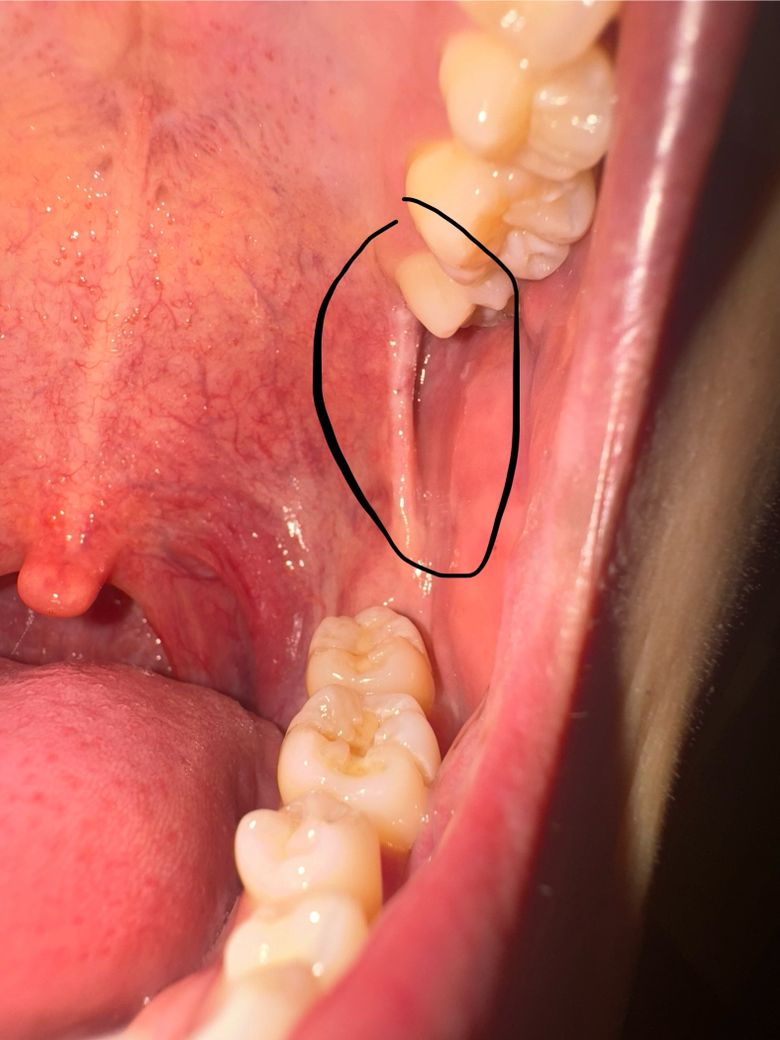

이 두 사진은 알보칠 바르기 전 사진입니다. 두달전에 아말감같은거 씌우러 치과에 간 뒤부터 저 끈?같은게 턱을 벌릴 때 땡긴다는걸 의식했었고 사랑니가 나는 자리(어금니 뒤쪽)에 흰색 뾰루지?같은건 그 전부터 있었던 것 같아요.(의식을 안하고있었어서 정확히는 모르겠습니다,,)

• 1번 째 사진

• 2번 째 사진